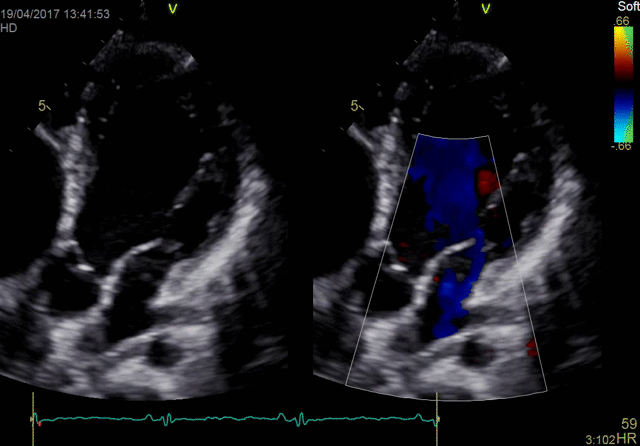

- Бескомпромиссный уровень качества визуализации как в двухмерном режиме, так и в режиме объемной реконструкции, а также гарантируя высочайшую чувствительность при цветовом картировании кровотока и допплерографии.

Экспертное качество изображений при проведении 2D TTE исследований и при обычной трансторакальной эхокардиографии дает возможность проводить сложные кардиологические исследования и получать достоверные результаты для назначения эффективного лечения.

Благодаря своим техническим возможностям система Vivid S70 позволяет получать достоверные данные для количественной оценки даже при проведении исследований пациентам с избыточным весом или пациентам состояние которых затрудняет проведение диагностики, а технология датчиков XDclear работающая в паре с платформой cSound гарантирует беспрецедентный уровень качества изображений.

- 4D TEE — благодаря высокопроизводительной платформе cSound выполнение объемной чрезпищеводной ЭхоКГ стало ощутимо легче, понятнее и быстрее. Для вас открыты широкие возможности просмотра высокоточных изображений сердца во время оценки его функций и диагностики в условиях эхолаборатории, уверенное выполнение манипуляций под ультразвуковым контролем при катетеризации или инвазивных хирургических вмешательствах в операционной.

Теперь вы можете использовать расширенные преимущества и искусственный интеллект системы Vivid™ S70N для ультразвукового исследования сердечно-сосудистой системы. Проводите диагностику с большей уверенностью благодаря усовершенствованным двухмерным и цветовым допплеровским изображениям. Уменьшайте время исследований с использованием детализированных автоматических измерений в допплеровском режиме при ЧПЭхоКГ и ТТЭхоКГ. Получайте воспроизводимые результаты с улучшенными характеристиками определения сердечной функции, в том числе фракции выброса. Все это помогает максимально эффективно использовать время, проведенное с пациентом: четко и быстро обнаруживать патологию, с высокой точностью выполнять манипуляции и обеспечивать медицинское обслуживание высокого качества.